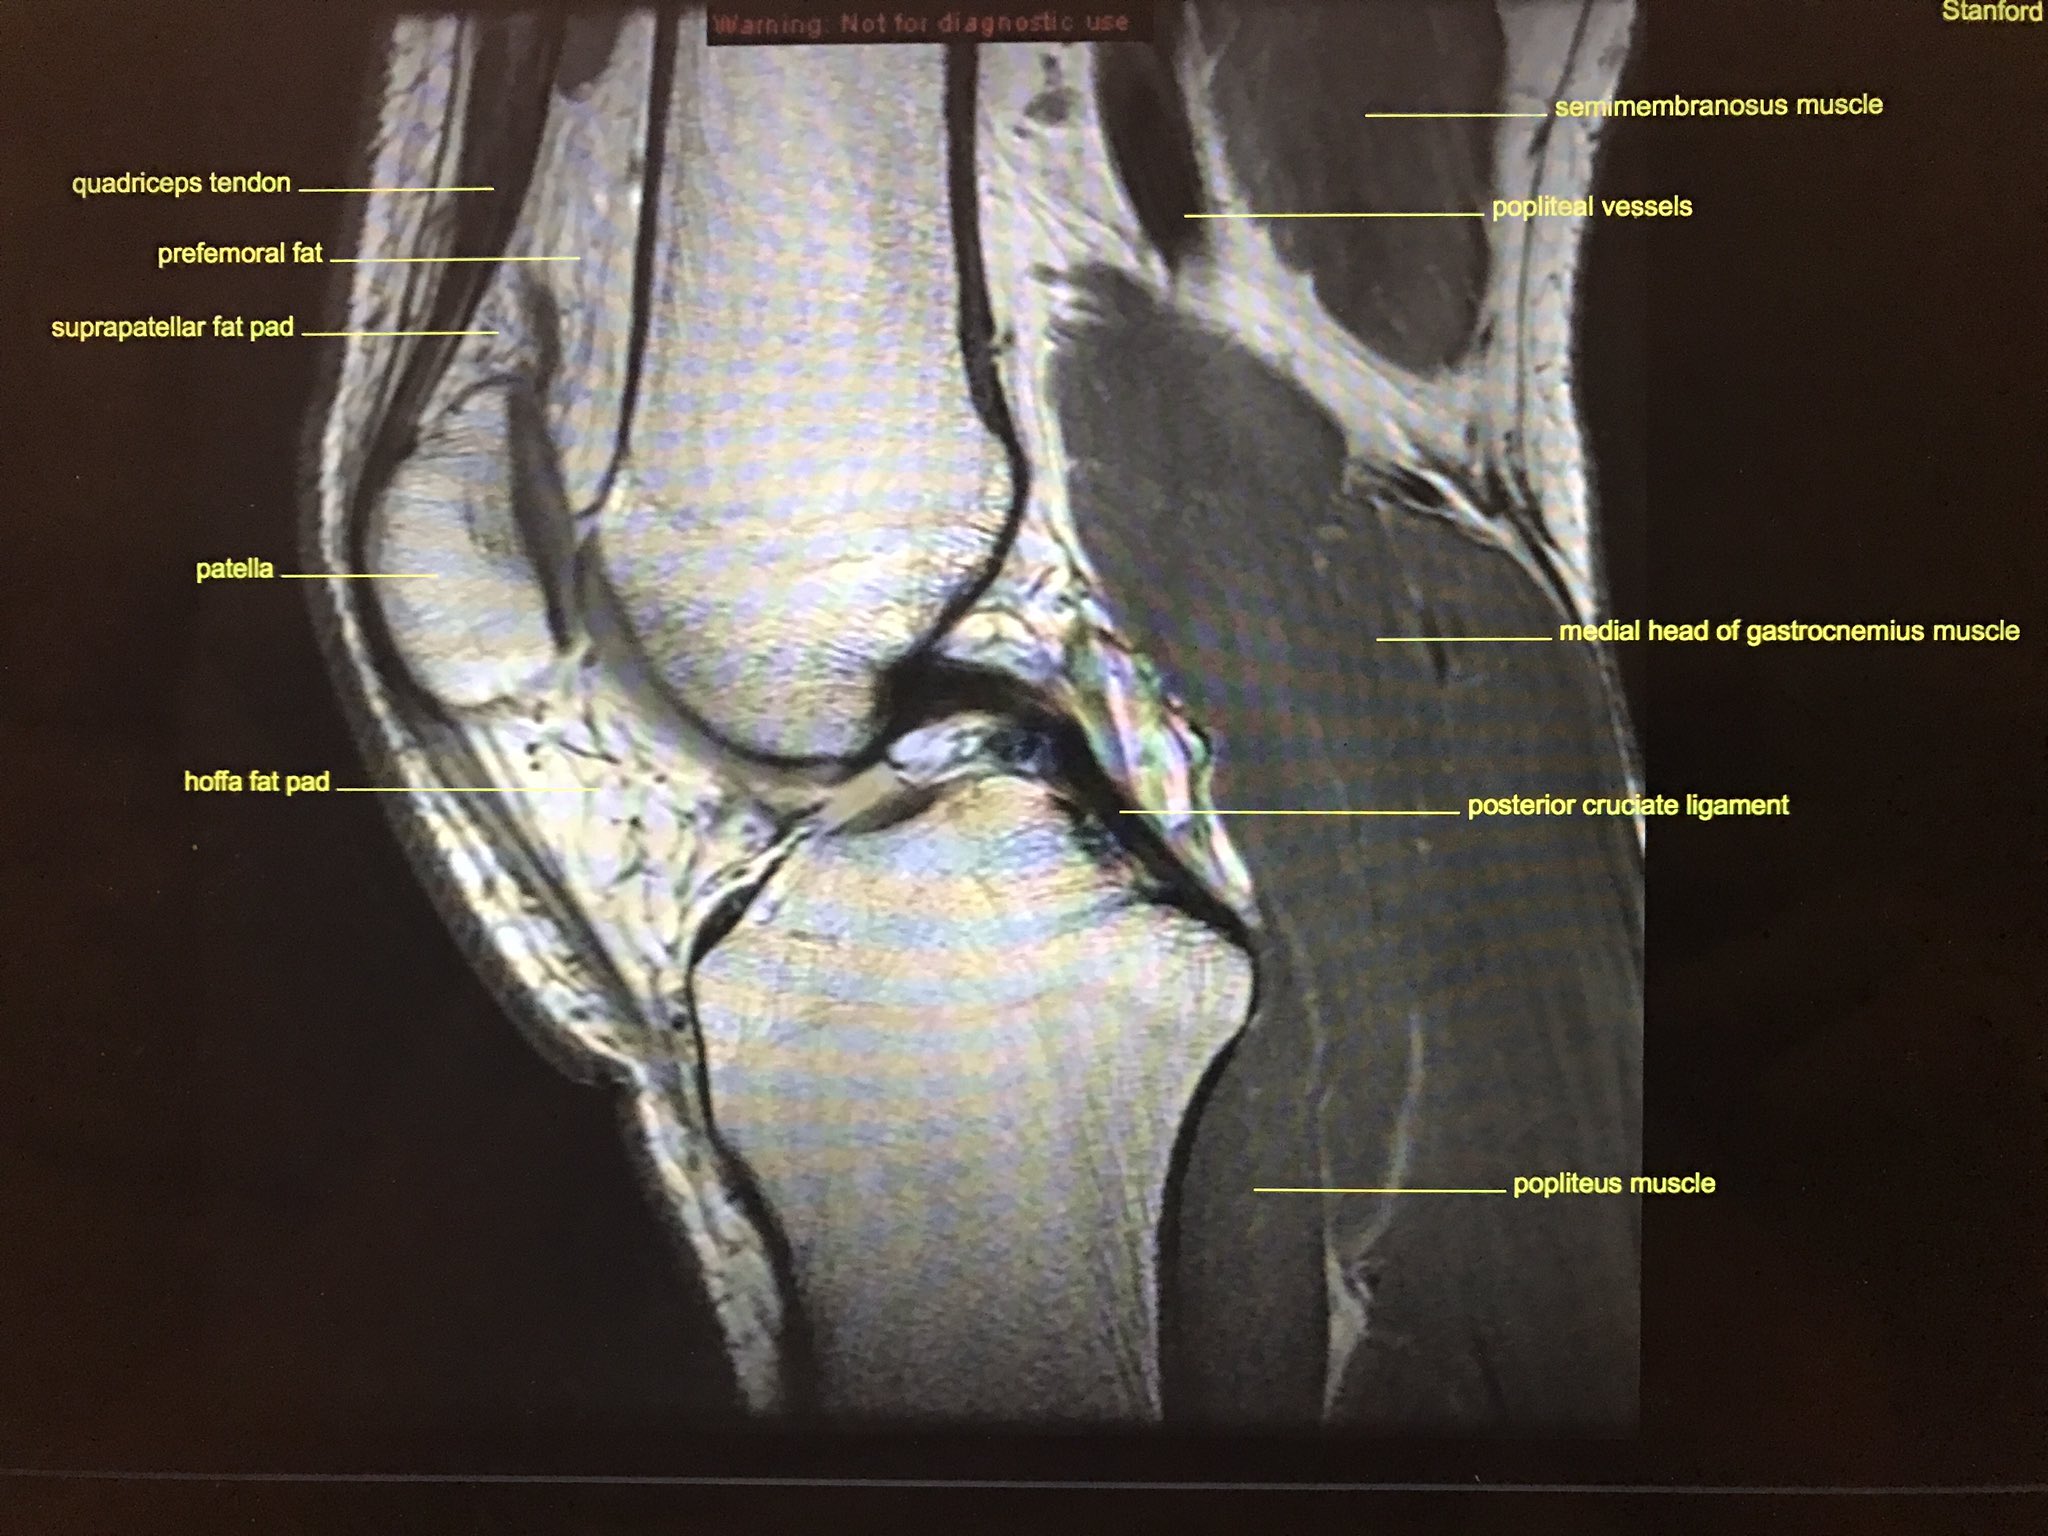

Knee anatomy francesc malagelada jordi vega pau golanó the knee is the largest joint in the human body and one of the most complex from a functional point of view. The knee joint is the junction of the thigh and leg. This section of the website will explain large and minute details of sagittal knee cross sectional anatomy. Injuries of the patellofemoral joint. Magnetic resonance imaging (mri scan):

Magnetic resonance imaging (mri) is a noninvasive test used to diagnose medical conditions. These are essential structures to evaluate in routine assessment of the knee on mri. Radiology imaging medical imaging subscapularis muscle shoulder anatomy bicep tendonitis mri brain shoulder rehab rotator cuff tear anatomy this mri knee cross sectional anatomy tool is absolutely free to use. Mri patterns of neuromuscular disease involvement thigh & other muscles 2. Free access interactive and dynamic anatomical atlas. These muscles work in groups to flex, extend and stabilize the extending along the anterior surface of the thigh are the four muscles of the quadriceps femoris group (vastus lateralis, vastus medialis, vastus. Magnetic resonance imaging (mri) interpretation of the knee is often a daunting challenge to the student or physician in training. Which are the ligaments that keep it stable? An understanding of normal anatomy and biomechanics of the knee extensor mechanism is necessary to comprehend the imaging of extensor mechanism injuries. Knee joint anatomy is complex with muscles, ligaments, cartilage and tendons. General anatomy and musculoskeletal system. This section of the website will explain. Use the checklist to quiz yourself.

Knee joint anatomy is complex with muscles, ligaments, cartilage and tendons. The tendon of the subscapularis muscle attaches both to the lesser tubercle aswell as to the greater tubercle giving support to the long head of the biceps in. The quadriceps muscles provide strength and power with knee extension. This webpage presents the anatomical structures found on knee mri. Learn about the muscles, tendons, bones, and ligaments that comprise the knee joint anatomy. Please email baodo at stanford.edu. This mri knee cross sectional anatomy tool is absolutely free to use. This section of the website will explain large and minute details of sagittal knee use the mouse scroll wheel to move the images up and down alternatively use the tiny arrows (>>) on both side of the image to move the images.

Mri for evaluating knee pain in older patients: The muscles that affect the knee's movement run along the thigh and calf. Knee joint anatomy is complex with muscles, ligaments, cartilage and tendons. Each anatomical structure was labeled interactively. How does the knee joint work? Please email baodo at stanford.edu. The knee joint is most significantly affected by two major muscle groups: These muscles work in groups to flex, extend and stabilize the extending along the anterior surface of the thigh are the four muscles of the quadriceps femoris group (vastus lateralis, vastus medialis, vastus. Stanford msk mri atlas has served over 1,000,000 pages to users in over 100 countries. Robin smithuis and henk jan van der woude. Which are the ligaments that keep it stable? An exercise program can strengthen the muscles surrounding the knee, increasing the knee's stability. Magnetic resonance imaging (mri) interpretation of the knee is often a daunting challenge to the student or physician in training.

They are attached to the femur (thighbone), tibia (shinbone), and fibula (calf bone) by fibrous tissues called ligaments. The journal of musculoskeletal medicine. Current and accurate information for patients about magnetic resonance imaging (mri)of the knee. Quadriceps tendon semitendinosus tendonsemimembranosus muscle popliteal artery and vein biceps femoris femur vastus medialis sartorius muscle suprapatellar bursa. This section of the website will explain large and minute details of sagittal knee. Scroll through the structures to understand the anatomy. Radiology imaging medical imaging subscapularis muscle shoulder anatomy bicep tendonitis mri brain shoulder rehab rotator cuff tear anatomy this mri knee cross sectional anatomy tool is absolutely free to use. An understanding of normal anatomy and biomechanics of the knee extensor mechanism is necessary to comprehend the imaging of extensor mechanism injuries. 4, infrapatellar fat pad of hoffa. Find out how the different structures fit together in our knee diagram the knee joint is the largest and one of the most complex joints in the human body. Located on the posterolateral aspect of the knee joint, extending from the popliteus muscle to the medial aspect of the fibula. Radiology imaging medical anatomy human anatomy and physiology anatomy study. The muscles that affect the knee's movement run along the thigh and calf.